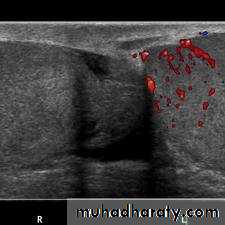

torsion of a testicular appendage.Color Doppler ultrasound .

radionuclide scanning .

In many hospitals these tests are not readily available and the diagnosis is based on symptoms and signs.